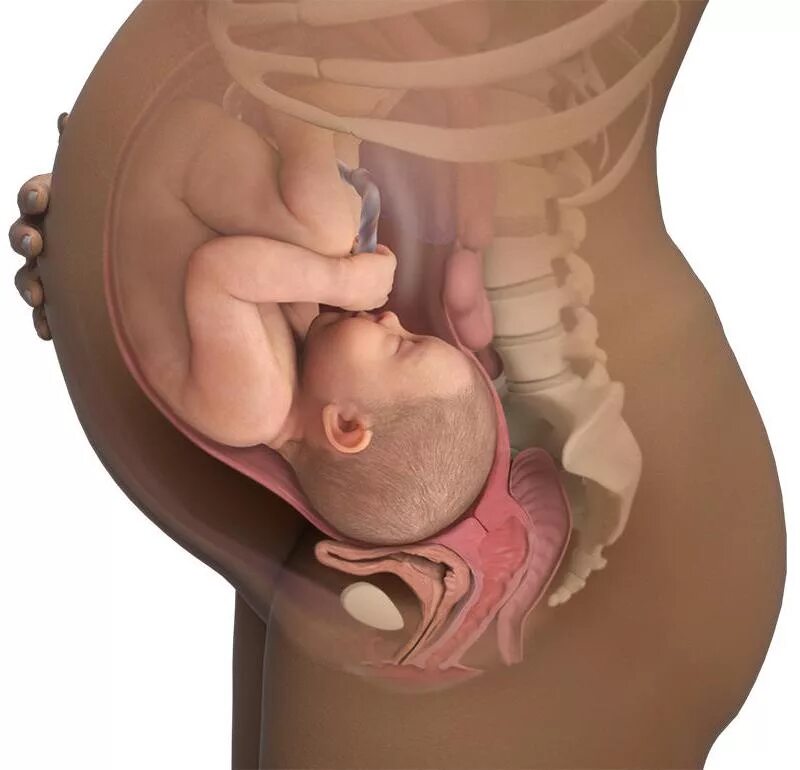

Ребенок 36 недель беременности в животе